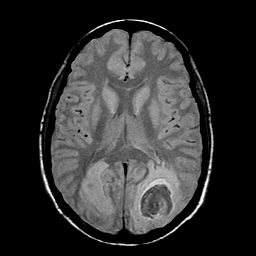

Sarcoma, MR Study #1 mr-pd -- Slice #13